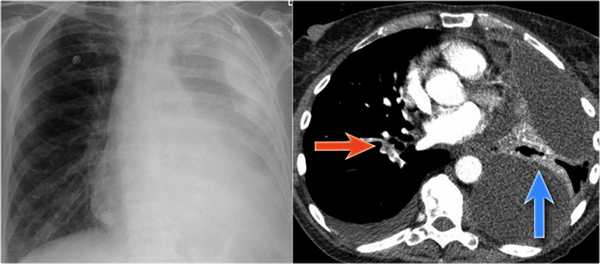

На ПЭТ/КТ визуализируется опухоль легкого с обструкцией правого верхнедолевого бронха, как следствие ателектаз верхний доли правого легкого.

Также очень частым проявлением ателектаза является подъем диафрагмы, что хорошо визуализируется на ниже представленной рентгенограмме (указано синий стрелкой).

У данного пациента карцинома легкого с билатеральным метастазированием в легкие (указано красными стрелкам).